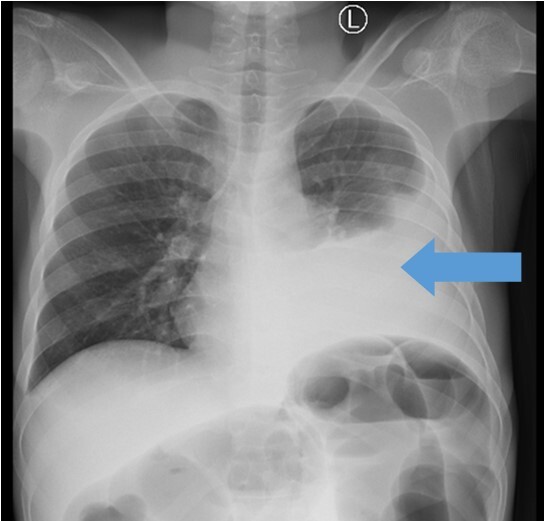

His complete blood count showed a hemoglobin of 9.4 g/dl (microcytic and hypochromic), leucocyte count of 9.22 × 109/l and a platelet count of 142×109/L. A plain chest x-ray revealed approximately 50% left pleural effusion (Figure 1), and abdominal-pelvic ultrasound concluded ascites, an ill-defined heterogenous pelvic mass with mild ascites. A contrasted CT-scan of the chest and abdomen showed symmetrical mural wall thickening measuring 4.2 cm of the sigmoid, upper, mid, and distal rectum measuring 16 cm in length, suggestive of a rectosigmoid tumor. The tumor was causing large bowel obstruction with ascites, and left sided pleural effusion (Figure 2).